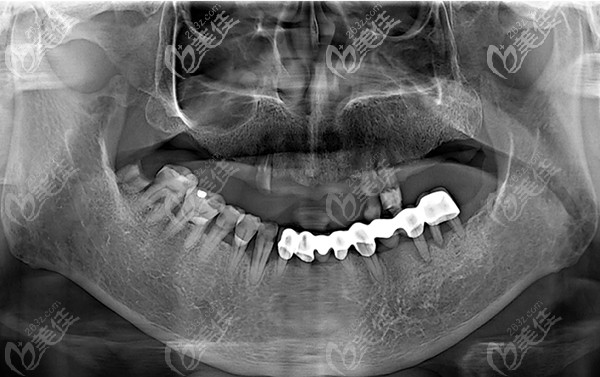

种植前牙片

要不是我这次特地带他去包头植诺口腔门诊做了一次牙齿检查,都不知道我爸的牙齿,因牙周炎导致牙齿出现松动掉落,想要修复已经无法保留了,需拔除后做种植牙才能修复。